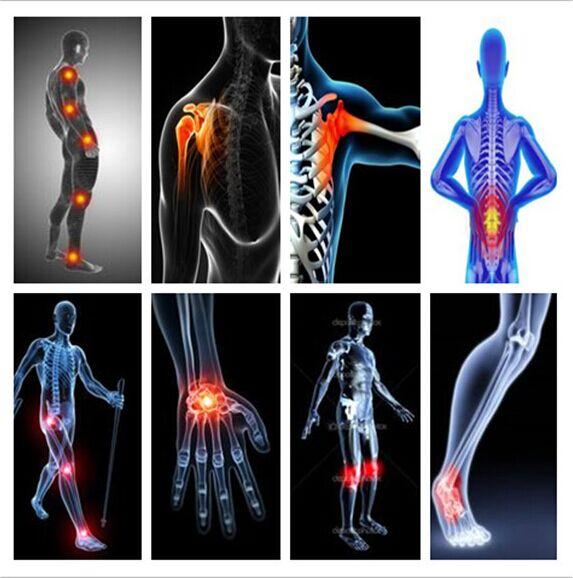

ESWT pain relief shock wave shoulder joint tendons shockwave treatment physiotherapy radial shock wave equipment

Extracorporeal Shockwave machine for pain therapy inflammations and calcification of shoulder joint tendons

Radial extracorpeal shockwave therapy system BS-SWT2T is for physiotherapy targets, as Radial and ulnar epicondylitis Tendinitis of the shoulder, Calcific tendinitis of the shoulder, Status post muscular injury, Patellar tendinitis, Patellar tendinopathy, Achillodynia, Plantar fasciitis, Heel spurs, Myofascial trigger point therapy e.g neck, Myofascial trigger point therapy e.g. back, muscular back pain, Trochanteric bursitis, Periostitis / shin splints (Condition after overload), Dupuytren's disease, Thumb basal joint arthritis / rhizarthritis, cellulite treatment, body shaping and slimming, connective tissue disorders.

Pain of the shoulder can be caused by e.g. calcifications, impingement syndrome or frozen shoulder. All the indications are a source of dull to severe pain and limit the patients in their daily life. In calcific tendonitis of the shoulder treated by the Shockwave the calcification disappears completely in more than 85% of the cases. Significant reduction in pain and improvement in shoulder function is observed after 4 weeks. Solution for a lot of cases is surgery or injections to which Shockwave therapy is a fitting substitute.

ESWT Physiotherapy shock wave machine Applications :